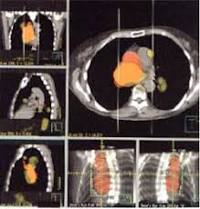

longitudinal. A esta técnica se la llama tomografía. Si la imagen

es de un plano transversal, es decir perpendicular al eje vertical del

cuerpo, y su análisis se realiza con una computadora, la técnica se

conoce como tomografía axial computarizada

cerebro